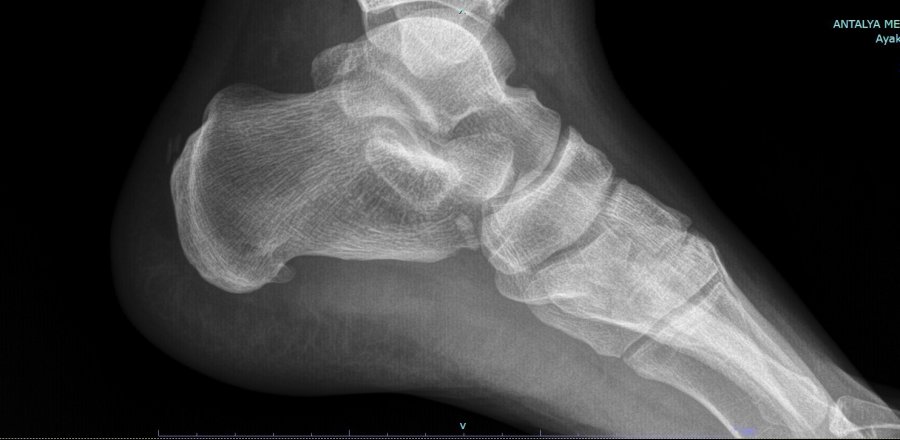

Tedavi yöntemleri hakkında da açıklamalarda bulunan Prof. Dr. Demiralp, "Ağrılı topuk sendromunun nedenlerine baktığımız zaman öncelikli olarak nedenini araştırmamız gerekir. Biz öncelikli olarak hastalarımızın şikayetlerini dinliyoruz. Ardından muayene yapıp gerekirse röntgen çekiyoruz. Burada en sık karşımıza çıkan plantar fascia dediğimiz ayakta gerginliktir. Ayakta yaşanan bu gerginliğin ardından uzun dönemde zarın çekmesiyle topuk kemiğinde uzaması sonucu gül dikenine benzer ince bir kemik yapı oluşturur" sözlerine yer verdi.

Hastanın iki dakikalık botoks yöntemi ile sağlığına kavuştuğunu belirten Prof. Dr. Demiralp, "Çeşitli tedavi yöntemleri olsa da biz daha çok botoks tedavisini tercih ediyoruz. Bu uygulama diğerlerine göre daha konforlu ve daha kısa sürede sonuç alabiliyoruz. Hastamızı muayene edip filmlerini gördükten sonra enjeksiyona karar verirsek, eğer tıbbı bir problemi yoksa botoks uygulamasını gerçekleştiriyoruz. Hastamıza uygun bir doz seçerek topuğa çok ince bir iğneyle botoks enjeksiyonu yapıyoruz. Amacımız gerginliğe sebep olan, topuk dikenine sebep olan Plantar Fasiitin gevşetilmesidir. Hasta birkaç gün içerisinde bu gevşemenin farkına varıyor. Ağrısı azalıyor. Çok uzun süre ağrısız bir dönem geçirebilir. Hastamız hemen normal hayatına dönebiliyor. Hiçbir kısıtlamamız yok. Cerrahi yöntemde ise hasta en az 2-3 hafta hayatını kısıtlayabilir. Her zaman cerrahiye ihtiyaç yoktur" açıklamasına yer verdi.